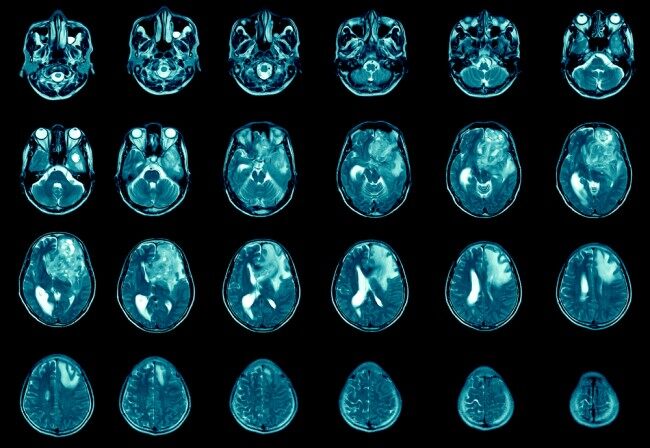

Dr Conchita Vens’ research will focus on glioblastoma, an aggressive form of cancer which mainly occurs in the brain and is currently difficult to treat. Finding new ways to tackle brain tumours is a key priority for Cancer Research UK.

In Scotland, around 32,400 people are diagnosed with cancer every year and one in two people in the UK will be diagnosed with cancer at some stage in their lives. Around 450 people are diagnosed with malignant brain tumours in Scotland every year, and every year around 390 people in Scotland die from the disease. Around one in 10 (9%) of people with a brain tumour survive for five years or more after diagnosis.

Currently, people with glioblastoma are treated with surgery, radiotherapy and chemotherapy.

Radiotherapy, combined with drugs like temozolomide, is the most common treatment option. However, not all patients can benefit from these drugs and brain tumours often return after treatment.